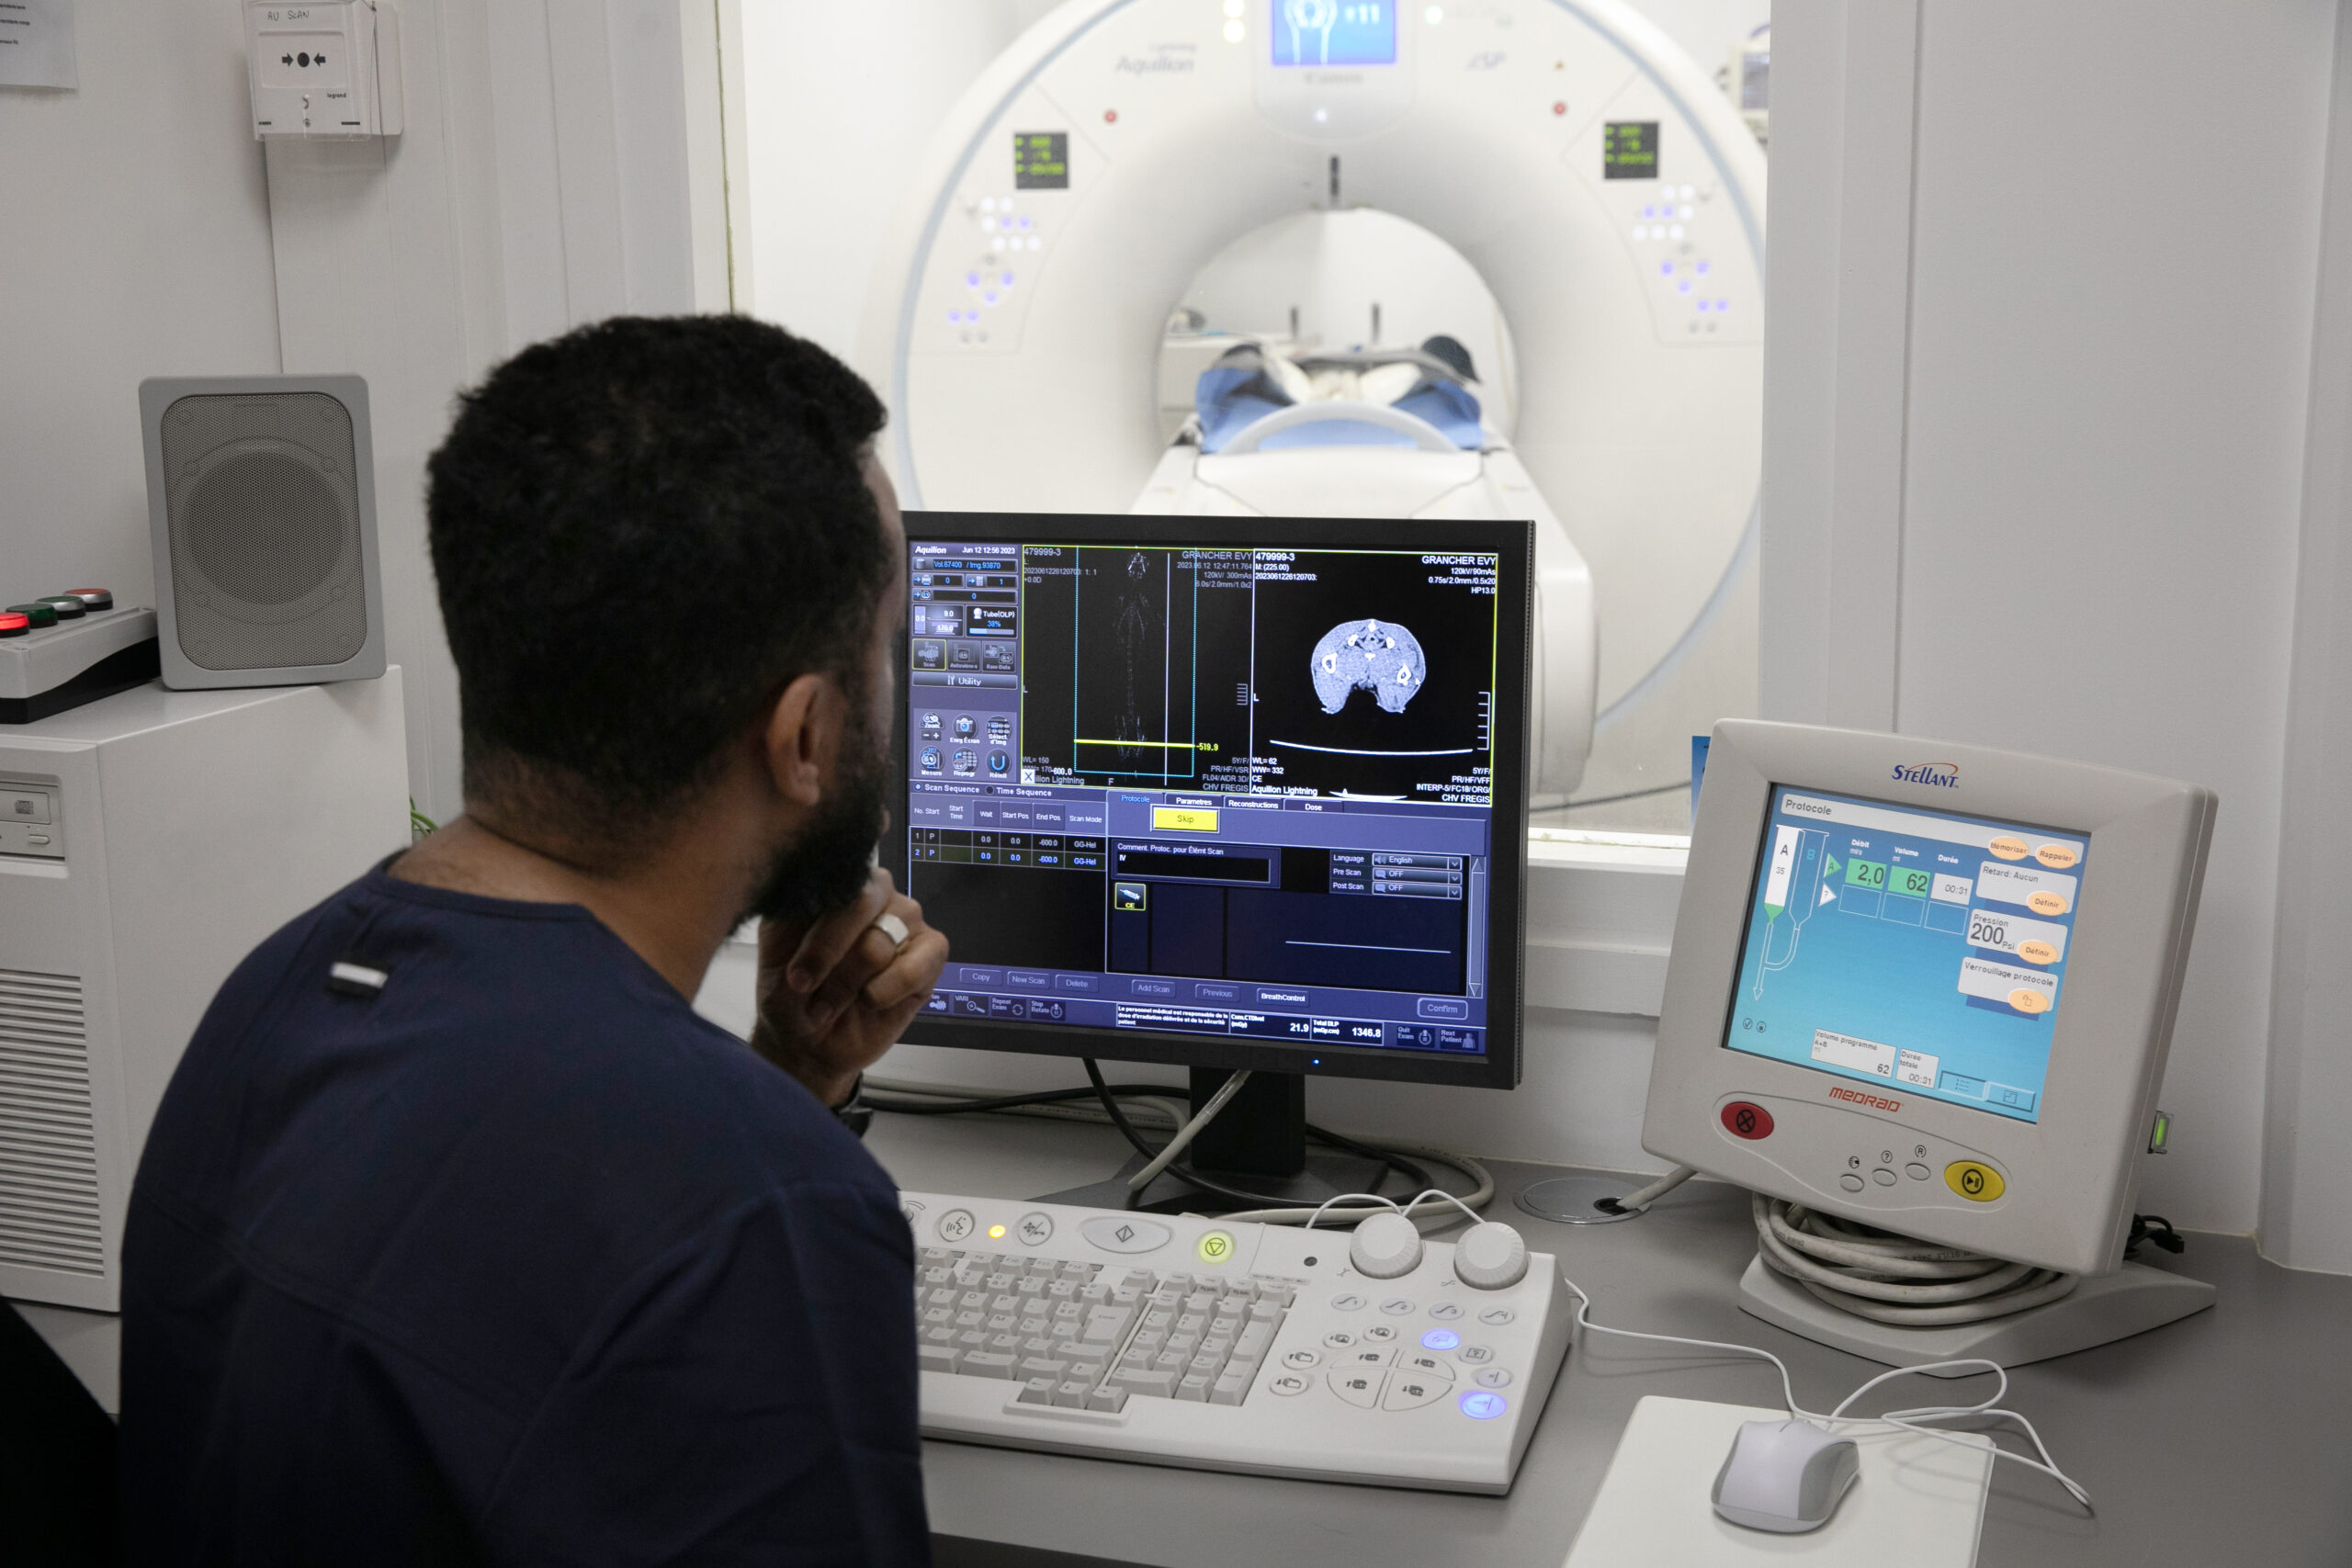

Le scanner

Le scanner

Tomodensitométrie

Utilisation des rayons X pour reconstituer des images en coupe des structures osseuses et à un moindre degré qualitatif des tissus nerveux cérébraux, médullaires et radiculaires.